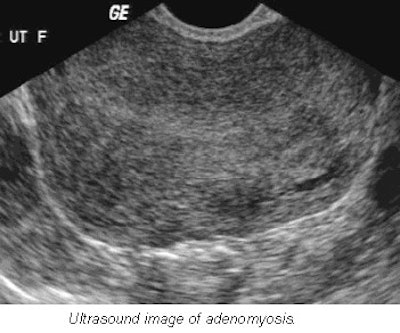

Lyons said his department was unfamiliar with the ultrasound appearances of adenomyosis, but a 1999 investigation at his institution changed all that. For this study, the group compared the sonograms of a series of patients with abnormal premenopausal bleeding with hysterectomy specimens, and developed ultrasound criteria for the differentiation of fibroids and adenomyosis.

- Women with adenomyosis are usually multiparous, while women with fibroids are more likely to be nulliparous. Lyons emphasized that "a fibroid is a clearly defined, easily identified mass, whereas adenomyosis is a diffuse infiltrative process."

- Fibroids can be hypoechoic, isoechoic (same echogenicity as myometrium), or hyperechoic. In comparison, the characteristics of adenomyosis include ill-defined regions of mixed textural changes, asymmetric myometrial thickening, streaky shadowing posteriorly, and no calcifications.

- Myometrial cysts, often in a subendometrial location and usually less than 3 mm in diameter, are commonly associated with adenomyosis. These cysts represent dilated endometrial glands that come and go during the menstrual cycle.